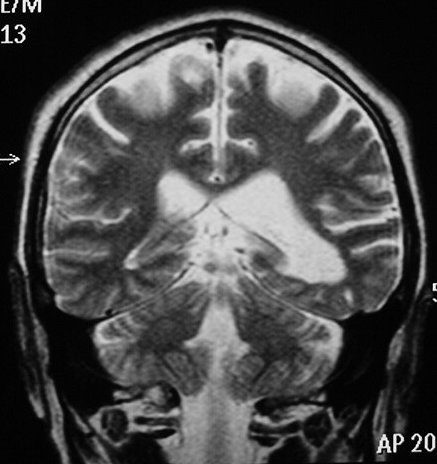

ГМ. Субэпендимома 2. +

Субэпендимома